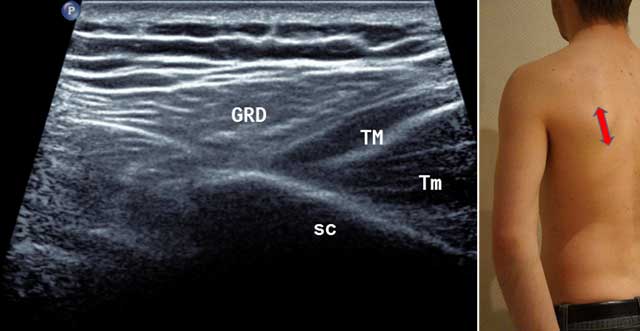

Sagittal medial cross section performed next to the lateral edge of the tip of the scapula allowing to distinguish the Teres Major from the Latissimus Dorsi (more superficial), in neutral or external rotation (Figure 2).

Figure 2

Sagittal oblique view of the scapula (Sc) in external position (red arrow). GRD: Latissimus Dorsi, TM: Teres Major, Tm: Teres minor.